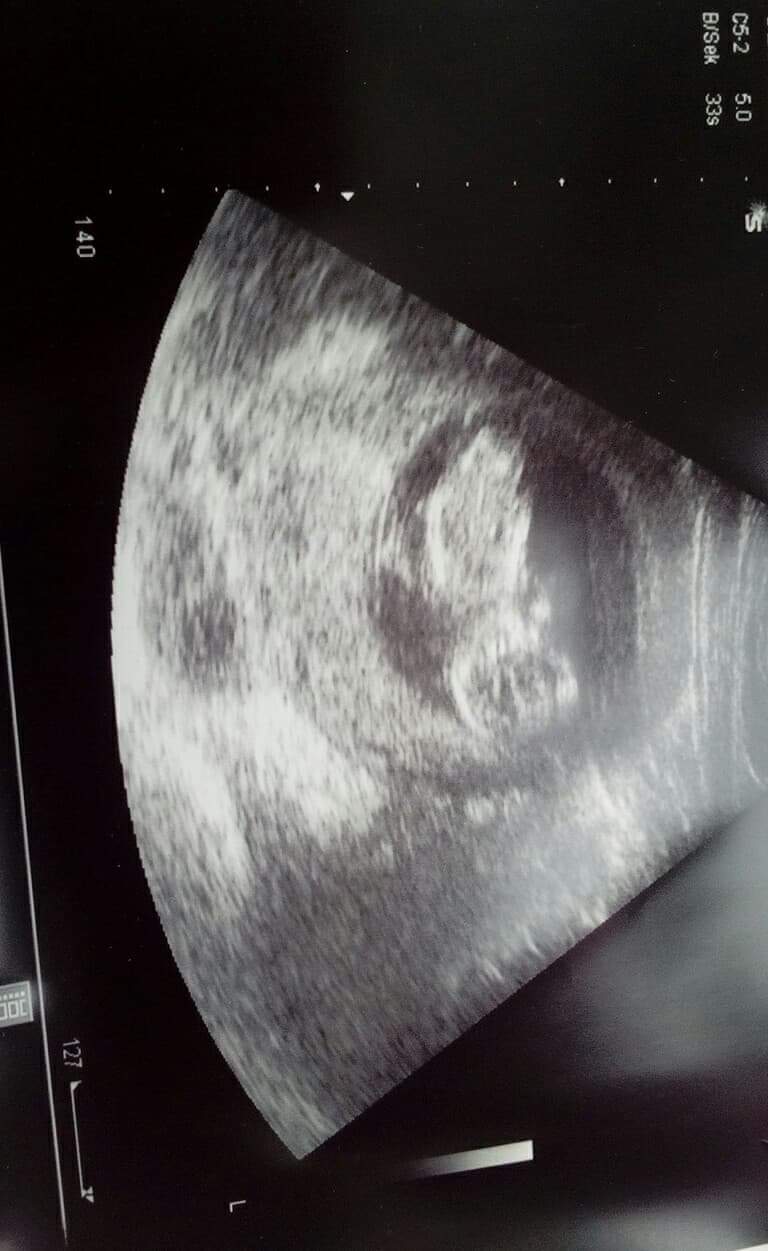

Witam w 19 tygodniu ciąży dowiedziałam się ze będę miała dziewczynkę w 20 tyg okazało się jednak , że to chłopak. Sama już nie wiem bo na jednym usg widać na pewno dziewuche a na drugim chłopca. Może to pempowina ?? Może ktoś mi pomoże rozwiązać ta zagadkę